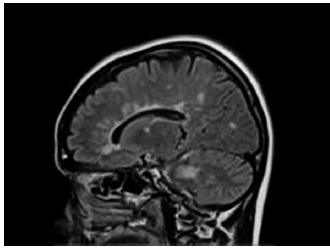

Mulher, 23 anos, comparece ao seu consultório com história de parestesias em pés e mãos de início há 6 semanas. O quadro progrediu para sensação parestésica até abdome; durou cerca de uma semana com resolução completa. Há duas semanas, voltou a apresentar parestesias em hemiface direita, com resolução completa em dois dias. Traz a seguinte ressonância de crânio.

Assinale a alternativa correta quanto à conduta inicial para essa paciente.